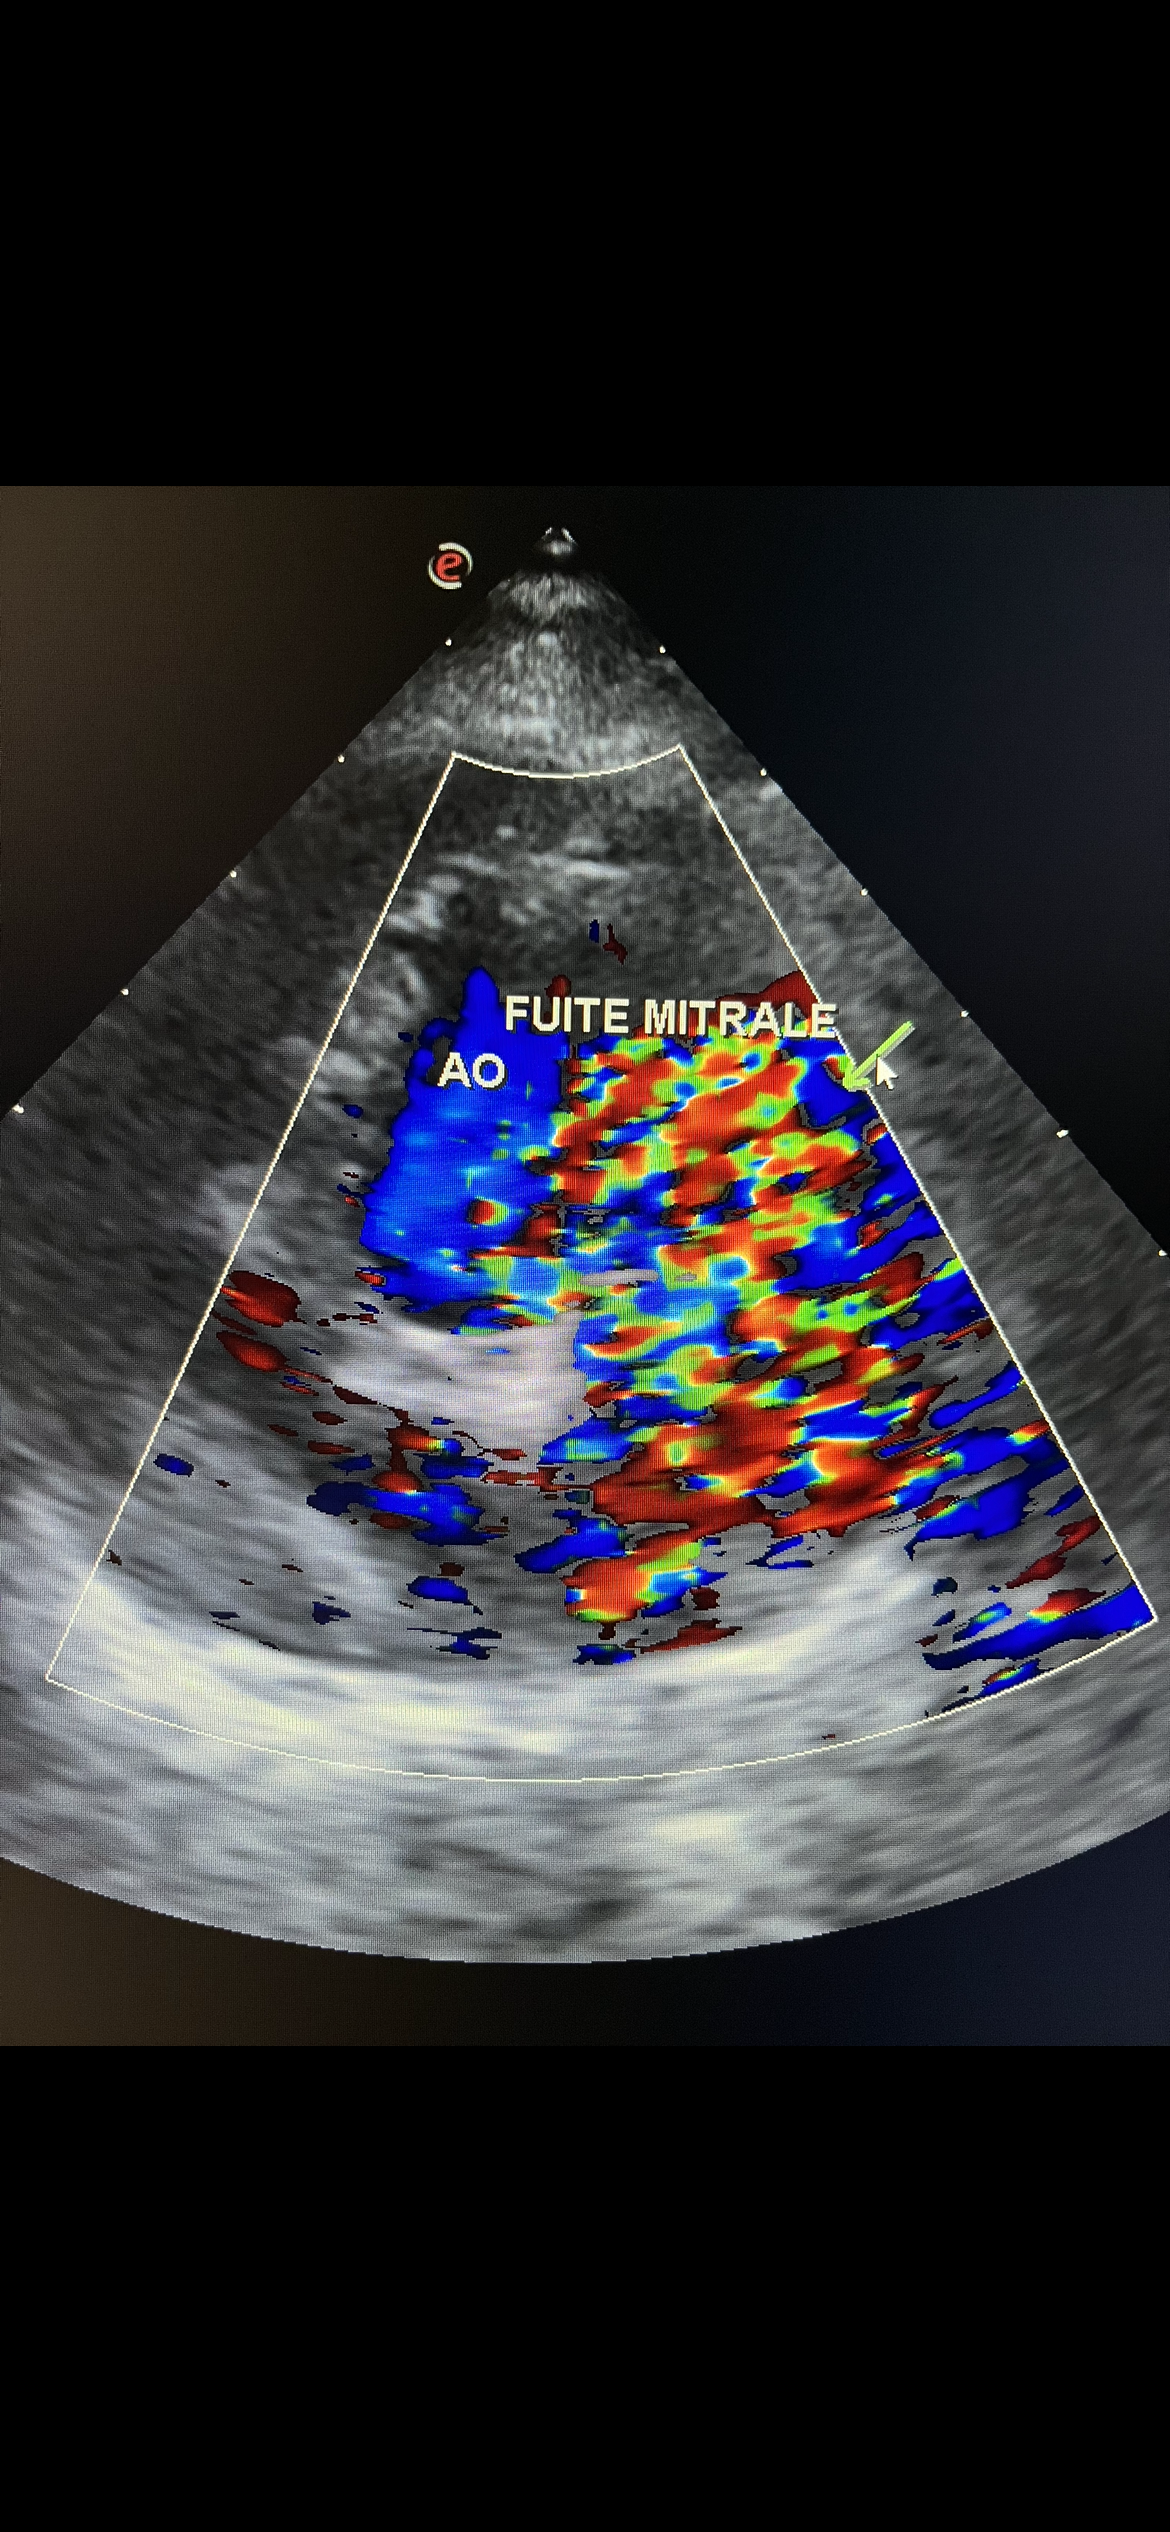

Un plateau technique de pointe